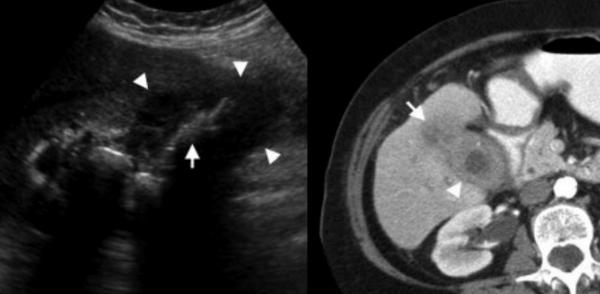

УЗИ и КТ желчного пузыря. Ксантогранулематозный холецистит. Слева на УЗИ визуализируется (помечено стрелками) утолщение стенки желчного пузыря с интрамуральным включением и с камнем в просвете органа. Справа на КТ выявляется утолщение стенки с гиподенсными включениями.